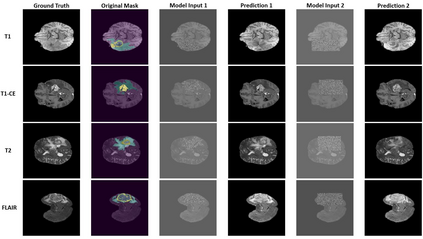

Despite the ever-increasing interest in applying deep learning (DL) models to medical imaging, the typical scarcity and imbalance of medical datasets can severely impact the performance of DL models. The generation of synthetic data that might be freely shared without compromising patient privacy is a well-known technique for addressing these difficulties. Inpainting algorithms are a subset of DL generative models that can alter one or more regions of an input image while matching its surrounding context and, in certain cases, non-imaging input conditions. Although the majority of inpainting techniques for medical imaging data use generative adversarial networks (GANs), the performance of these algorithms is frequently suboptimal due to their limited output variety, a problem that is already well-known for GANs. Denoising diffusion probabilistic models (DDPMs) are a recently introduced family of generative networks that can generate results of comparable quality to GANs, but with diverse outputs. In this paper, we describe a DDPM to execute multiple inpainting tasks on 2D axial slices of brain MRI with various sequences, and present proof-of-concept examples of its performance in a variety of evaluation scenarios. Our model and a public online interface to try our tool are available at: https://github.com/Mayo-Radiology-Informatics-Lab/MBTI